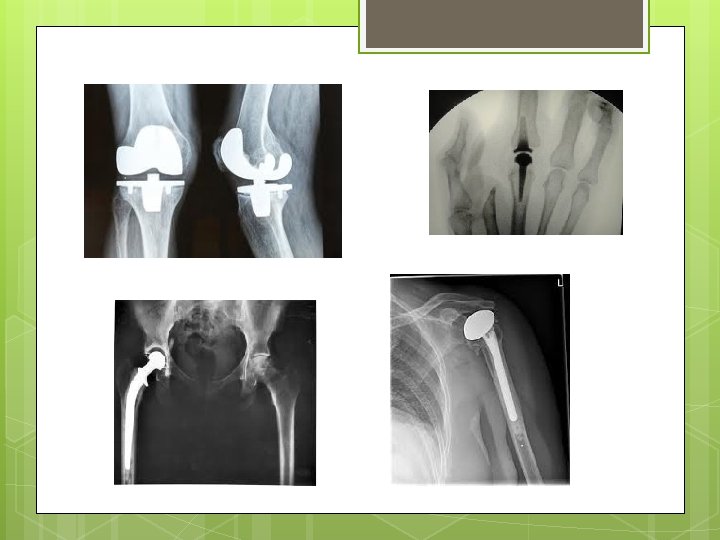

Joint Replacement Surgery The arthritic joint parts are replaced by metal or plastic parts. Hospital stay 3 to 4 days according to healing process. Low complications